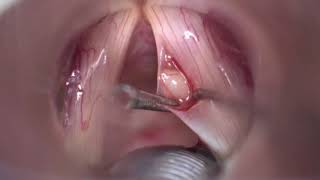

WebUna lesión reactiva de las cuerdas vocales es una masa situada frente a una lesión de las cuerdas vocales, como un quiste o pólipos. Este tipo de lesión se cree que se. WebLas microsinequias son membranas de pequeña superficie (2-4 mm) que unen las cuerdas vocales a nivel de la comisura anterior. La membrana redondea el ángulo. WebOtros nombres: Extirpación de quistes o formaciones cuerdas vocales o epiglotis. Microk¡laringoscópia. Los quistes de cuerdas vocales son casi siempre unilaterales..